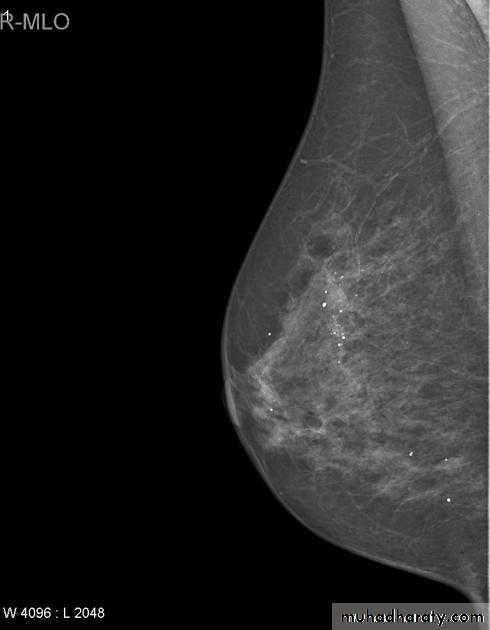

The mediolateral oblique (MLO) view is one of standard mammographic views. It is the most important projection as it allows to depict most breast tissue.

The sensitivity of mammography for the detection of ILC reportedly ranges between 55-80% 8. Because of the limitations of mammography in detecting ILC, other modalities, such as sonography and MR imaging, are being used in evaluating clinically suspicious findings and known cancers to assess the extent of disease. ILC are more commonly seen on the craniocaudal (CC), compared to the mediolateral oblique (MLO).

Micro calcifications

Micro calcifications are tiny specks of calcium in the breast. Micro calcifications seen on a mammogram are of more concern than macrocalcifications, but they do not always mean that cancer is present. The shape and layout of microcalcifications help the radiologist judge how likely it is that cancer is present.